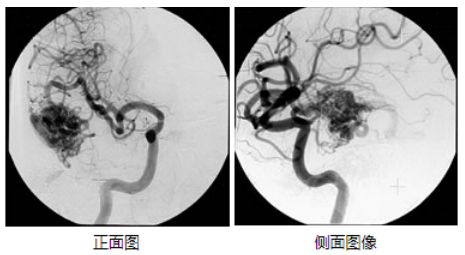

治療結(jié)果根據(jù)病變的大小和部位有很大的差異,據(jù)報道,γ刀治療的直徑3cm以內(nèi)的腦動靜脈畸形的情況下,3年后的五年生存率約為60%-90%前后。下圖為伽馬刀治療成功并完全阻塞的典型案例-伽瑪?shù)赌X血管造影術(shù)。